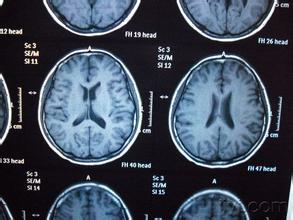

(1)脑结构影像检查

①头颅CT;

②头颅MRI。